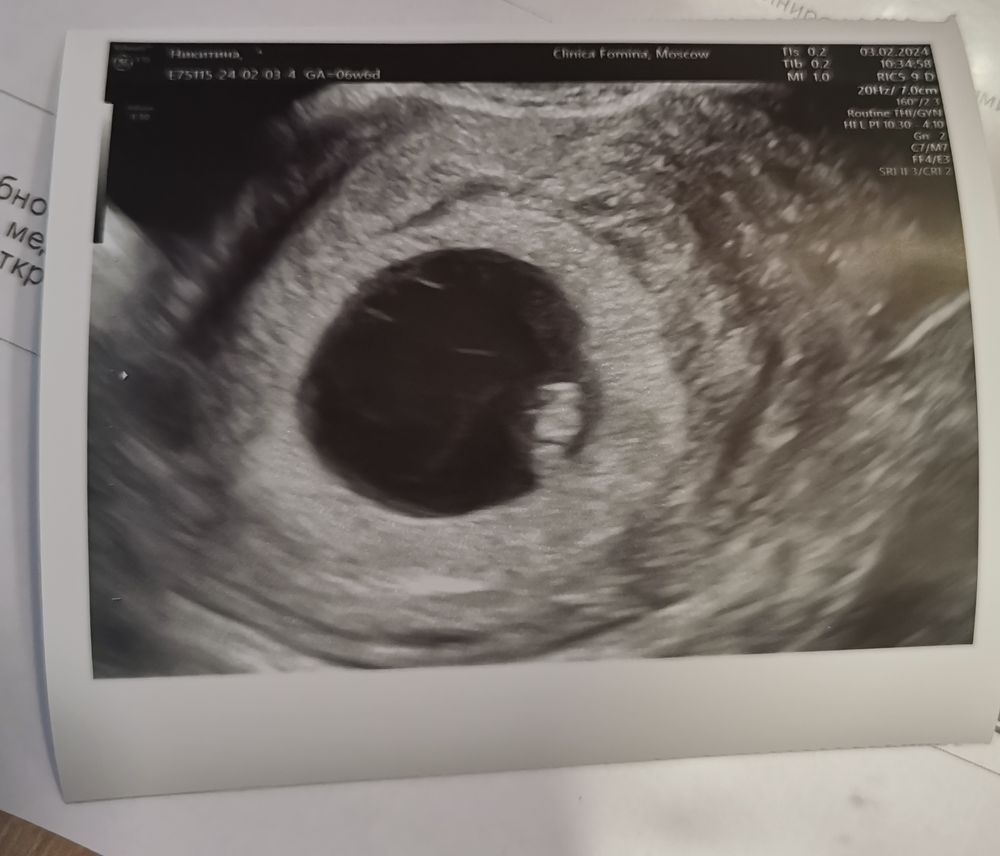

Узи 6+6. Сердечко ❤️ и эмбрион

У нас получилось! Я беременна!Сходила в субботу на узи с мужем. Специально выбирала клинику где можно снимать и заходить с мужем. Выбор пал на клинику Фомина. Врач все подробно посмотрела, рассказала. По итогам ктр 7,4 мм, сердечко 139 ударов. Прикрепление по задней стенке. Все соответствует сроку😊 Никаких гематом, отслоек и тонусов 🥰 На память теперь у меня не только фото бусинки, но и видео ❤️